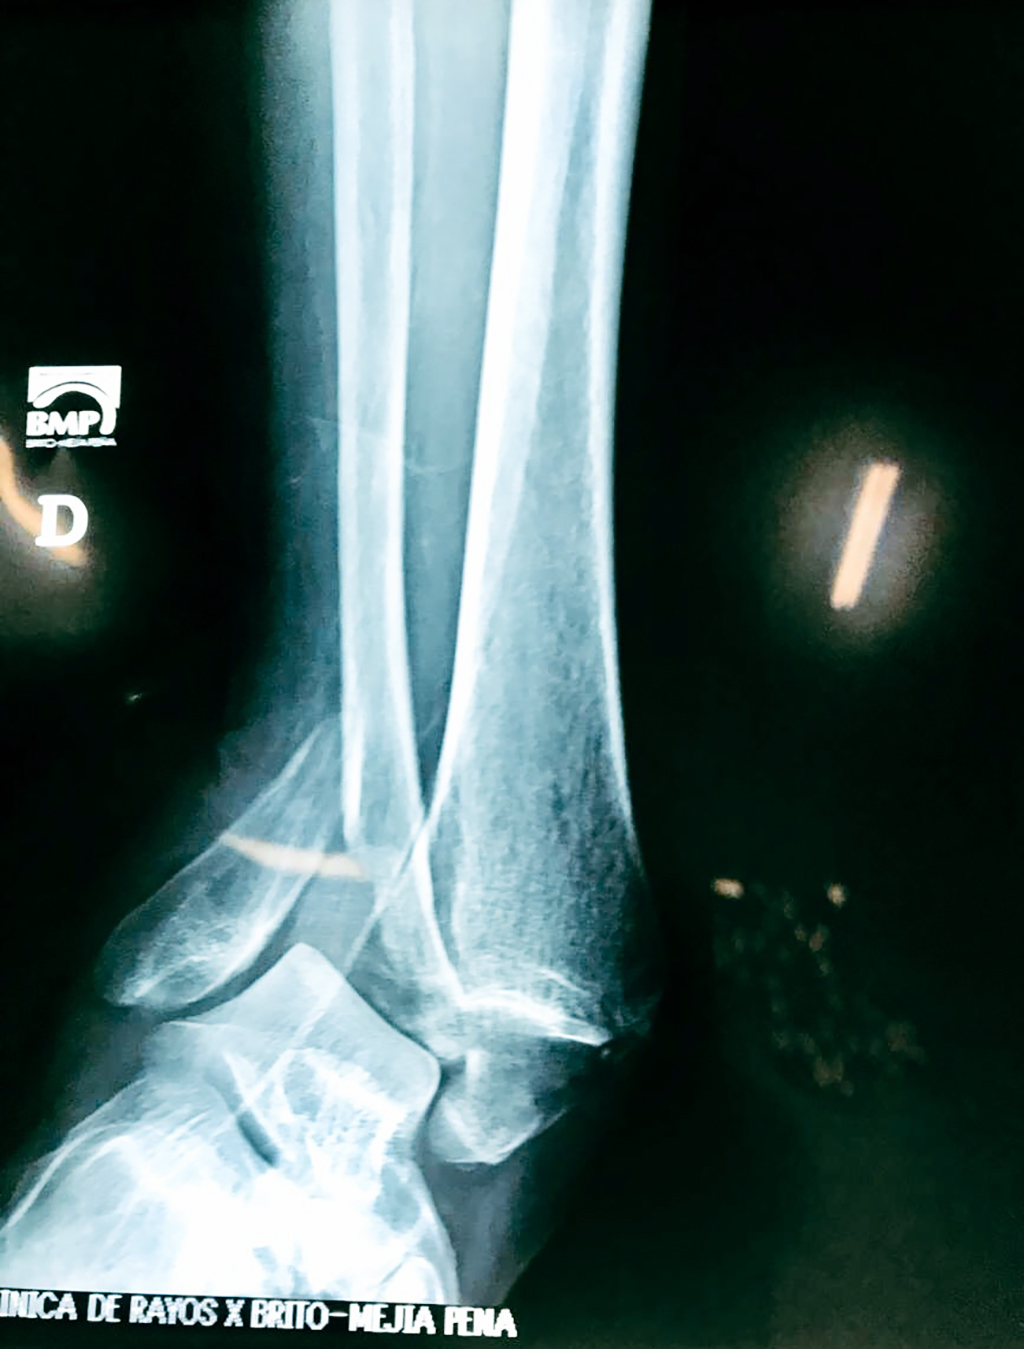

Una fractura de tobillo es la rotura de uno o más de los huesos del tobillo. Estas fracturas pueden ser:

- Parciales (el hueso está sólo parcialmente fisurado, no del todo).

- Completas (el hueso está perforado y está en 2 partes).

- Producirse en uno o ambos lados del tobillo.

Algunas fracturas de tobillo pueden requerir cirugía si:

- Los extremos de los huesos están desalineados entre sí (desplazados).

- La fractura se extiende hasta la articulación del tobillo (fractura intra-articular).

- Los tendones o ligamentos (tejidos que sujetan los músculos y los huesos entre sí) están rotos.